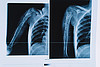

После обследования пациента было принято решение о госпитализации и проведении остеотомии, то есть удлинению сегмента при помощи спицевого аппарата. Операция по удлинению верхней трети плечевой кости продолжалась около полутора часов. Специалистами Центра травматологии было произведено рассечение плечевой кости и установка спицевого аппарата внешней фиксации для дистракции – растяжения и удлинения кости. Для образования регенерата растяжение выполнялось по 1 миллиметру в сутки. Пациент провел с аппаратом на плече 5 месяцев, за это время укорочение было компенсировано на 7,5 сантиметров.

В ноябре 2022 года на плановой госпитализации рентген-контроль показал, что плотность сформированного регенерата удовлетворительная. Пациенту был удален аппарат внешней фиксации. В настоящее время юноша чувствует себя хорошо, отмечает, что даже болевых ощущений после снятия аппарата не испытывал. Сейчас он вернулся к полноценной жизни.